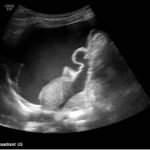

A 5-month-old female presented to the emergency department with worsening abdominal distention and postprandial emesis. Point-of-care ultrasound (POCUS) demonstrated extensive abdominal free fluid with a large, heterogeneous mass in the suprapubic region. This was confirmed on computed tomography (CT) of the abdomen and pelvis. The patient was urgently taken to the operating room for exploratory laparotomy where a ruptured tumor was discovered. The patient was eventually diagnosed with ovarian juvenile granulosa cell tumor. POCUS can be vital in guiding the recognition of rare pediatric conditions in the emergency department and should be considered in patients where there is concern for an acute abdomen.